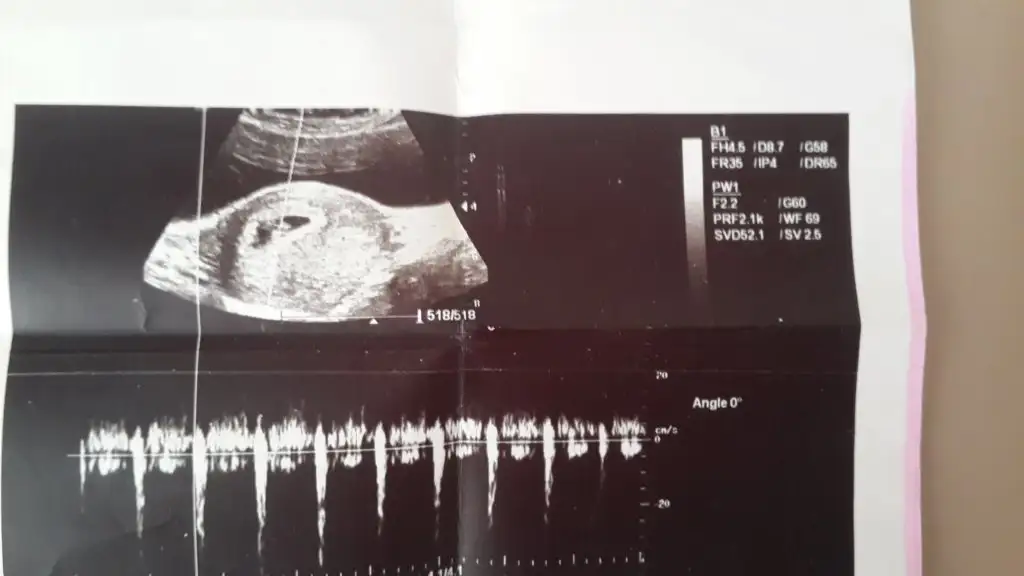

Kizlar sizce benim bebeisimin cinsiyeti nedir burada 7 haftaliktii..

Burda tam 6+6. Bende anlamadim. Karindan ya da vajinal farkli oluyor diye okuyunca sastim kaldim. Ikinci hamileligim. Ilk bebegim erkekti. Ve o sagdaydi. O yuzden isin icinden cikamadim. Ikiside farkli olunca acaba cinsiyeti farkli mi diye dusundum. Baska yardimci olabilecek arkadaslar varsa cvp bekliyorum

Arkadaslar 7 haftalık usg resmim bebis 8 mm oldugu icin daha net

kızlar buda benim 10 haftalıkken usg resmim... vajinal baktı doktorum... solda duruyor benimkide